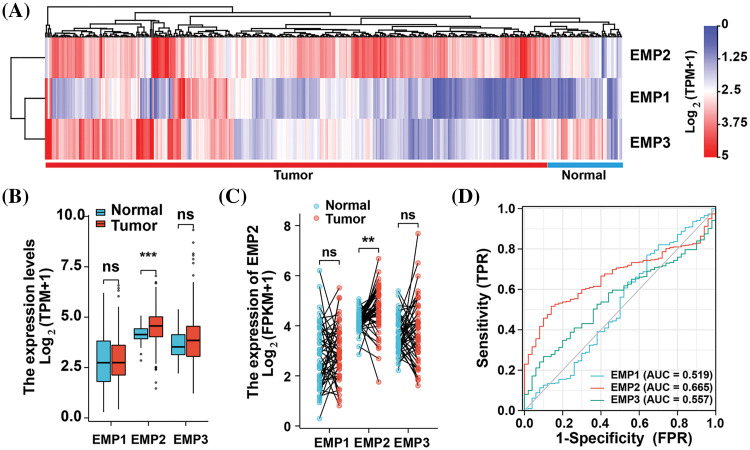

To investigate the expression patterns of EMP1, EMP2, and EMP3 in hepatocellular carcinoma (HCC) and normal liver tissues, we analyzed mRNA expression data from 374 HCC patients obtained from The TCGA database. EMP1, EMP2, and EMP3 expression was detected in all 374 samples, which included 50 paired samples of HCC tissue and adjacent non-cancerous tissue. The analysis revealed distinct expression patterns for these genes. EMP1 demonstrated high expression in a small proportion of HCC tissues, while exhibiting extremely low levels or no expression in normal liver tissues and most HCC tissues. Conversely, EMP2 exhibited the opposite pattern, with minimal or no expression in normal liver tissues and high expression in most HCC tissues. In contrast, EMP3 displayed a more dispersed expression pattern, with no significant differences between tissue types. EMP3 exhibited high expression in some tumor and normal tissues, while also showing low or no expression in other tumor and normal liver tissues (Fig. 1A). Differential expression analysis of EMP1, EMP2, and EMP3 in the 374 HCC tissues compared to 50 adjacent non-cancerous tissues was performed (Fig. 1B). The average Log2 (TPM + 1) expression level (TPM, transcripts per million) of EMP1 in the Normal group was 2.788 ± 1.279, while in the Tumor group, it was 2.858 ± 1.131. Despite the slightly higher expression levels in the Tumor group compared to the Normal group, the difference was not statistically significant (p > 0.05). Similarly, EMP3 exhibited higher expression in the Tumor group compared to the Normal group, but the difference was not statistically significant (p > 0.05). In contrast, EMP2 demonstrated significantly higher expression in the Tumor group, with an average Log2 (TPM + 1) of 4.516 ± 0.803 compared to 4.165 ± 0.411 in the Normal group (p < 0.001). These findings suggest that EMP2 may play a crucial role in liver tissues.

To comprehensively assess the differential expression of EMP1, EMP2, and EMP3 in HCC and normal liver tissues, we performed additional analysis on 50 paired HCC tissues and adjacent non-cancerous tissues to determine their mRNA expression levels (Fig. 1C). The results demonstrated that EMP2 expression levels were significantly higher in the Tumor group compared to the Normal group. The median difference in EMP2 expression between the two groups was 0.518, which was statistically significant (p = 0.001). In contrast, EMP1 and EMP3 expression levels in the Tumor group were only marginally higher than those in the Normal group, and these differences were not statistically significant (p > 0.05). To evaluate the predictive performance of EMPs expression in HCC, we performed a receiver operating characteristic (ROC) curve analysis and validated the results (Fig. 1D). Regarding the ability to predict HCC, EMP2 demonstrated superior diagnostic efficacy compared to EMP1 and EMP3. These findings suggest that EMP2 has a moderate level of predictive performance, which may have clinical implications in the diagnosis of HCC compared to EMP1 and EMP3. Importantly, EMP2 exhibited significant upregulation in HCC tissues, suggesting its potential role in HCC development.